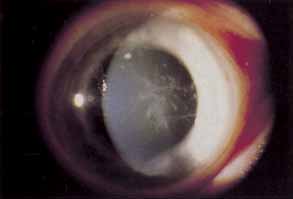

EPITHELIUM The corneal epithelium bears the brunt of mechanical trauma and chemical alterations meted out during contact lens wear. Hypoxia is emerging as a major force in corneal epithelial damage not explainable by direct trauma related to lens defects or handling. Decreasing dK in rigid lenses in an animal model increased the observed degree of corneal epithelial cell swelling and desquamation.78 Extended soft contact lens wear has been implicated in specular microscopic observations of enlarged surface epithelial cells, suggesting a slower turnover of cells under these conditions.79 Even scant concentrations of common contact lens disinfectants, which come into intimate contact with the epithelial surface on a daily basis in hydrogel lens wear, cause epithelial cell retraction and decreased mitotic activity.80 The spectrum of corneal epithelial injury secondary to contact lens wear extends from mild punctate epithelial keratopathy in specific patterns to severe ocular surface disorders with indolent ulceration, anterior stromal scarring, superficial vascularization, and decreased vision requiring surgical intervention.81 There has even been a report of intraepithelial neoplasia associated with contact lens wear in the setting of extensive acute ultraviolet radiation exposure.82 Because isolated trauma to the epithelium may lead to serious corneal scarring, persistent contact lens abuse may lead to visual loss requiring penetrating keratoplasty.83,84 With enough foresight most contact lens wearers may avoid these devastating results. PUNCTATE EPITHELIAL KERATOPATHY Punctate epithelial keratopathy (PEK), or superficial punctate keratitis (SPK) to which it is often incorrectly referred, may result secondary to trauma, hypoxia, drying, chemical toxicity, or any permutation of the previous list.9,85 Discontinuing lens wear, eliminating potentially toxic topical medications, and treating tear surface abnormalities are the mainstays of therapy for these findings. Specific changes in contact lens material, fit, care, or wearing time may be required to prevent recurrence. Contact lens overwear produces a coarse central pattern of staining that is often associated with excessive rigid and soft contact lens wear as well as with flat-fitting rigid lenses.9 The severity of staining is proportional to the duration of contact lens abuse and will determine recovery time following discontinuing lens wear. Discontinuing extended wear, decreasing daily wear time and refitting with steeper rigid lenses are all possible approaches to prevent recurrence.26 The presence of an arcuate patch of PEK near the superior limbus is suggestive of hypoxia secondary to a tight upper lid.9 This may be addressed by refitting with higher dK lenses or decreasing the duration of continuous lens wear. Contact lens-related superior limbic keratoconjunctivitis presents with additional signs and symptoms to accompany the irregular superior PEK that develops in noncontact lens-related SLK.9,74,75 The diagnosis and treatment of this condition have been discussed previously under conjunctival complications. Corneal PEK secondary to solution toxicity commonly presents as a diffuse pattern of superficial punctate fluorescein staining involving the entire corneal surface, often including the limbal conjunctival surface as well.9 Patients complain that the lenses sting immediately upon insertion. Review of lens care protocol is critical to eradicate this complication. Hand washing should be doubly stressed. Dendriform punctate epithelial keratopathy occurs in the setting of severe contact lens solution toxicity or hypersensitivity.9,86–88 These dendriform lesions are slightly raised epithelial plaques that stain lightly with fluorescein (Fig. 2). In contrast, dendrites related to herpes simplex keratitis are intensely staining true ulcers and exhibit terminal bulbs. An association with contact lens solutions preserved with thimerosal and chlorhexidine has been suggested. Lens discontinuation and supportive therapy with nonpreserved tears and ointments constitute effective therapy. Lenses may be reintroduced using nonpreserved saline and thermal disinfection. Significant delay in diagnosis or persistent lens wear, in spite of these findings, may result in permanent stromal scarring beneath the dendriform epitheliopathy. Treatment with antivirals is not helpful and may worsen subsequent subepithelial scarring. Foreign body patterns of epithelial staining are similar to those seen with embedded foreign bodies in the upper tarsal conjunctiva. Contact lenses must be carefully inspected for embedded foreign bodies, tears, or nicks. Trapped debris under the lens is more commonly associated with rigid lens wear and may also cause this staining pattern. This finding may be avoided by attending to cleanliness at the time of lens insertion, avoiding contact lens wear for activities involving airborne foreign material, and controlling the amount of makeup applied to the lid margins. Three and nine o'clock staining occurs commonly with rigid lens wear but may occur with soft lens wear as well.9 Pie-shaped wedges of PEK appear at the nasal and temporal limbus as a result of poor wetting of the local epithelium. Patients with pronounced against-the-rule astigmatism are more susceptible to this type of staining because of the bearing pattern of the lens. Persistent lens wear, in spite of this staining, may result in scarring and rarely pseudopterygia formation.89 Susceptible patients may develop raised scarring consistent with Salzmann's nodular degeneration. Refitting smaller diameter lenses with thinner edge design may eliminate mechanical trauma related to friction from the lens edge. Cases in which astigmatism is contributory may be addressed by using back-toric lens designs or soft-lens piggyback systems. Inferocentral patches of PEK occur secondary to desiccation associated with contact lens- related dry eye or exposure. Supplemental lubrication during lens wear may be required to prevent recurrence. Decreasing wear time or switching to low water content, soft lenses may also improve results. Contact lens wear may be salvaged by permanent punctal occlusion in selected cases of aqueous deficiency dry eye. Topical cyclosporin-A drops (Restasis) may be used to restore enough tear production to allow continued lens wear. Punctate epithelial keratopathy is a common finding often neglected as minor in the grand scheme of complications related to contact lenses. Remember that persistent epithelial staining puts the wearer at risk for microbial keratitis and may, when it progresses to coarse punctate erosions, represent the early stages of pseudomonas or acanthamoeba keratitis.90–92 ABRASIONS Corneal abrasions may be caused by lens defects or may occur during lens insertion or removal. Abrasions occur more frequently with rigid lens wear because lens defects have sharp edges and foreign material gains access to area under the lens more easily.6 Corneal abrasions with soft lens wear are seen most frequently with tight lenses or extended wear lenses. In these situations acute epithelial hypoxia impairs epithelial attachment to Bowman's layer. Treatment is the same as that for noncontact lens-related abrasions. Careful examination of the lens and its fit and queries to the patient regarding techniques of lens removal are important to identify causes of recurrent abrasions. EPITHELIAL EROSIONS Extended wear soft contact lenses are often used as a therapeutic modality for recurrent erosions resistant to medical therapy with topical hypertonic saline. However, animal studies suggest that extended contact lens wear worsens epithelial adhesion.93 This may explain the occasional contact lens intolerance seen with anterior epithelial basement membrane dystrophies.94 The osmotic effects of high water content, ultra-thin soft bandage lenses may counteract the effect of decreased adhesion by dehydrating the epithelium; however, this desiccation may, in turn, promote the formation of coarse punctate erosions in the central and paracentral cornea.9 These erosions are less likely to occur under highly humid conditions. Epithelial erosions related to extended contact lens wear elevate the risk of pseudomonas keratitis and should be treated accordingly.95 MECHANICAL INDENTATIONS There are two distinct types of epithelial wrinkling, both of which are considered benign and non-progressive.9 The first type, called anterior corneal mosaic, may be induced in normal eyes by applying pressure externally or reducing intraocular pressure. This mosaic pattern occurs in association with rigid lenses that have significant central bearing, such as those fit for apical bearing in keratoconus.96 The pattern quickly resolves with removal of the lens but may persist in the presence of abnormally low intraocular pressure. The second type of wrinkling produces criss-crossing furrows on the epithelial surfaces that pool fluorescein.9,97 Extended wear, ultra-thin soft contact lenses are implicated as the cause of these furrows, which are deeper and fade more slowly than those related to rigid lens wear. Corneal wrinkling, also referred to as the “rippling phenomena,” is not associated with progressive changes of the corneal surface and does not necessitate lens removal.97 Air bubbles trapped beneath rigid lenses between blinks will form small indentations in the epithelial surface called dimples.9 Dimpling occurs in PMMA lens wearers most frequently but can rarely be found in soft lens wearers. No treatment is required. Persistent pressure of the edge of a rigid lens may leave an arcuate furrow or ring on the corneal surface.9 This lens edge imprint typically lies inferior in the cornea but may represent the entire lens. Entire lens imprints are more commonly found with PMMA lenses and extended wear, gas-permeable, rigid lenses that adhere to the corneal surface during sleep.37,38 Recurrent lens imprints may result in corneal distortion that over time may become permanent. Further discussion of the implications and treatment of corneal distortions related to contact lens wear will be addressed in the section entitled “Corneal Deformation: Corneal Warpage and Keratoconus.” EPITHELIAL MICROCYSTS Epithelial microcysts form in response to the hypoxia of soft contact lens wear.9,98–100 They appear after 6 to 8 weeks of lens wear and appear as translucent dots that show reversed illumination when viewed in retroillumination. They may be confused with lesions found in Meesmann's epithelial dystrophy but will resolve with proper care. The prevalence and severity are inversely proportional to lens dK and proportional to lens wearing time. Altering either of these parameters in a patient who has developed greater than 50 microcysts or whose cysts begin to stain with fluorescein will cause gradual reduction of the number of microcysts within 3 months. Rarely lens wear must be discontinued. SUPERFICIAL NEOVASCULARIZATION Superficial corneal neovascularization is a response to persistent hypoxia secondary to contact lens wear (Fig. 3).9,101–103 Rigid lenses rarely develop limbal hyperemia greater than normal controls. Daily wear–lens patients will often show an apparent increase in limbal vascularization, which actually represents limbal capillary dilation and rarely progresses to frank neovascularization. Extended-wear soft contact lens wearers most often exhibit significant limbal new vessel growth. Topical nonsteroidal antiinflammatory agents may suppress neovascularization, but their use has not become routine.104 Most often treatment consists of changing from extended to daily wear schedules, fitting with higher dK or thinner lenses or fitting with a looser soft lens. The use of soft extended wear lenses after penetrating keratoplasty is particularly risky because of the rapid neovascular response observed.105 HYPOESTHESIA Corneal hypoesthesia is most commonly associated with PMMA contact lens wear.9,106 This complication explains the blissful ignorance of some more severe complications by the average PMMA lens wearer. Refitting with gas-permeable rigid lenses restores corneal sensitivity of these patients within 2 to 3 weeks.107 Soft contact lens wear has been implicated in corneal hypoesthesia to a degree less than PMMA lens wear, and the hypoesthesia is inversely proportional to the oxygen transmissibility of the lens.9,108 Corneal hypoesthesia contributes to the osmotic effects of contact lens wear by decreasing reflex tear secretion.9 |